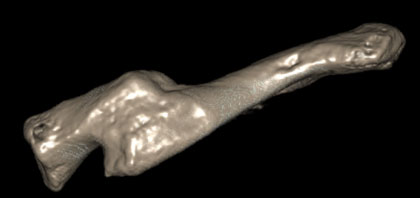

After seeing Joe, I arranged a 3D CT scan to visualise the bone and a CT angiogram to assess the location of the blood vessels surrounding the injury.

These images show clearly the deformity and shortening of the clavicle, and allow careful planning for a surgical procedure. After discussing his options with me, Joe decided to proceed with an operation to correct the malunited fracture. The first step of the operation was to re-break the clavicle at the site of the old fracture, allowing the bone to be brought out to its normal length. A plate and screws were inserted to hold the bone in its correct, anatomical position. A local bone graft was then used after collecting bone around the old fracture site to encourage healing of the old fracture ends.

3D CT scan and 3D model of  clavicle malunion used to plan surgery